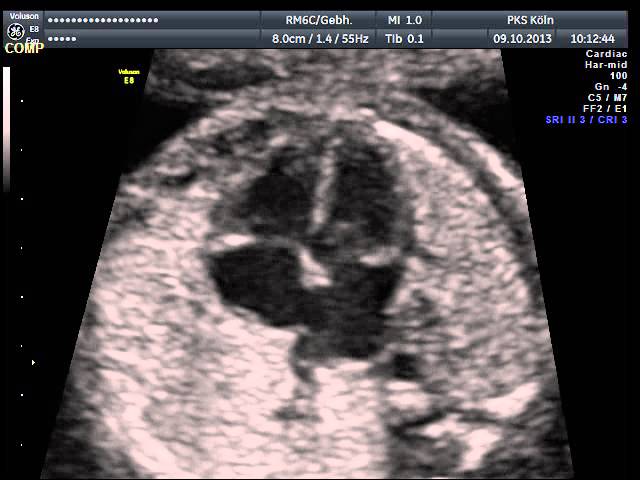

Das Entdecken und die Beurteilung von fetalen Herzfehlern erfordert ein hohes Maß an Untersuchungserfahrung und eine entsprechende Geräteausstattung, sodass sie häufig im Rahmen von Routineuntersuchungen nicht erkannt werden. Daher sollten gerade Eltern mit einem erhöhten Risiko für fetale Herzfehler diese Untersuchung des kindlichen Herzens durchführen lassen.

Alle Untersuchungen werden an High-end-Geräten durchgeführt, die technisch auf dem allerneuesten Stand sind. Diese Untersuchung kann bei entsprechender Indikation mit Überweisung vom betreuenden Frauenarzt erfolgen oder als Wunschleistung ohne Indikation.